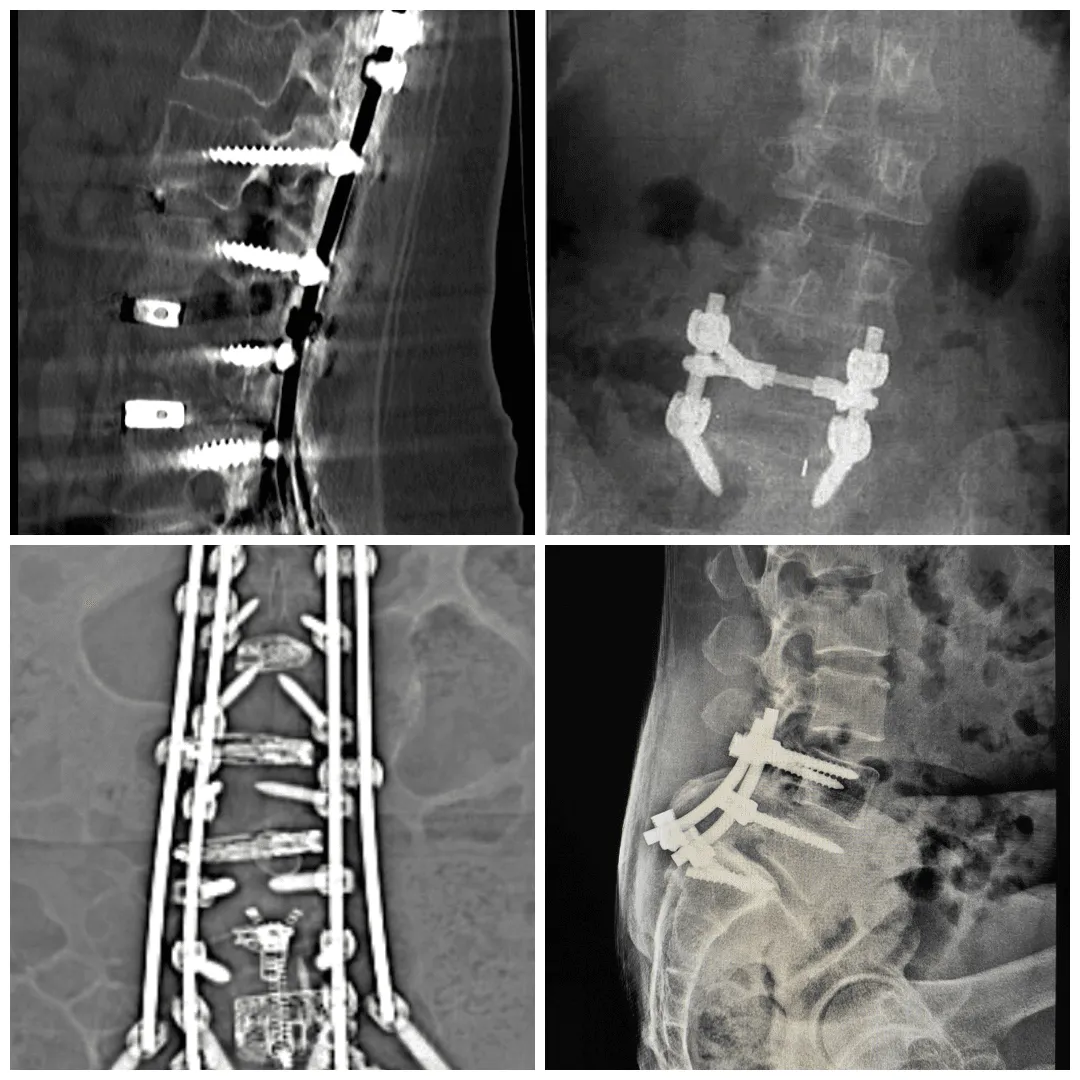

3. Traditional Spinal Fusion

Spinal fusion involves removing the disc, placing bone graft material between the vertebrae, and securing the construct with metal hardware including screws, rods, and cages. The adjacent vertebrae are permanently joined as a single solid bone segment. Fusion is appropriate for conditions involving true spinal instability, spondylolisthesis with significant slippage, or severe deformity that requires structural correction.

For disc displacement without spinal instability, fusion is generally not the optimal treatment. It permanently eliminates motion at the fused level, transfers biomechanical stress to adjacent segments, and carries a well-documented risk of adjacent segment disease. Recovery takes 6 to 12 months and involves extensive activity restrictions. Hardware complications including screw loosening and cage subsidence require reoperation in a meaningful percentage of patients.